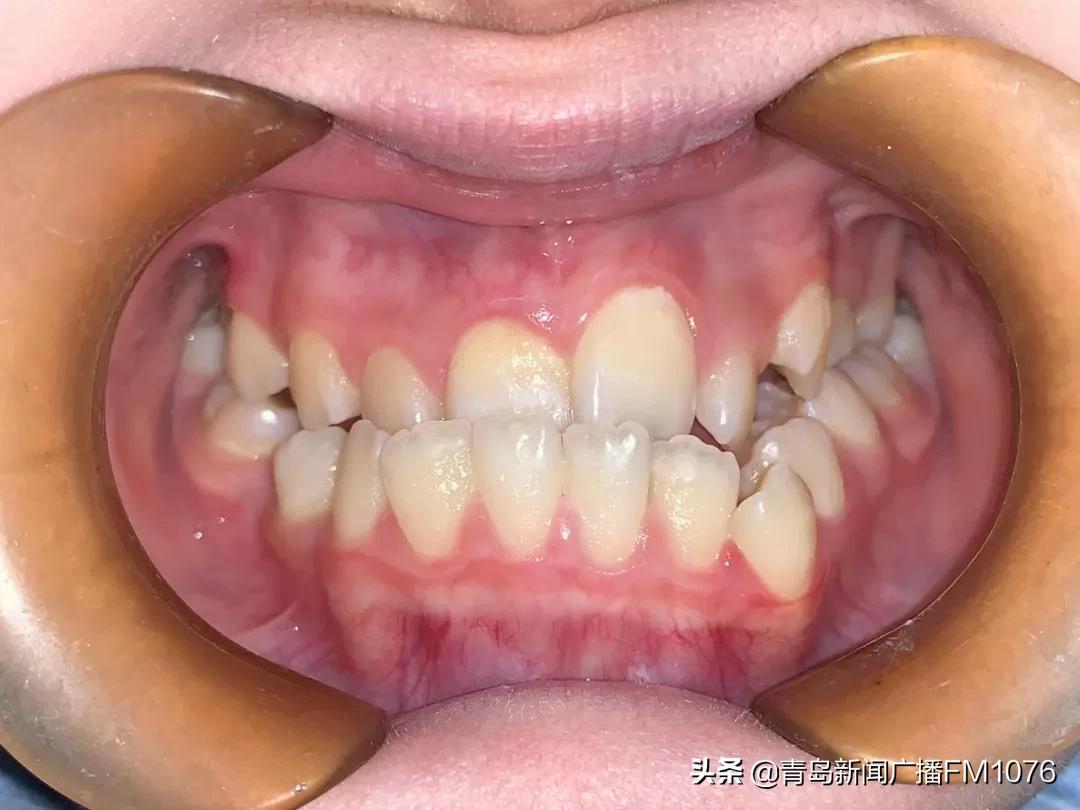

牙頜畸形的危害主要表現(xiàn)在美觀和功能兩個(gè)方面,但家長(zhǎng)和孩子往往只關(guān)注美觀方面而忽略了功能方面的問(wèn)題。比如后牙鎖牙合這種情況,上下后牙一個(gè)頰向傾斜錯(cuò)位一個(gè)舌向傾斜錯(cuò)位,兩個(gè)牙齒沒(méi)有咬合接觸,雖然有這兩顆牙齒,但沒(méi)有功能,沒(méi)法咀嚼吃飯,這個(gè)后牙鎖牙合牙齒情況現(xiàn)在發(fā)病率很高,并且很容易被家長(zhǎng)和孩子忽視。前牙開(kāi)牙合往往上下牙齒排列挺整齊,但前牙沒(méi)有咬合接觸,也無(wú)法咬合接觸,喪失了前牙切割動(dòng)作的咬合功能,也容易被忽視。對(duì)于孩子的牙齒是不是需要矯治要綜合考慮,必要時(shí)候咨詢(xún)一下正畸醫(yī)師的專(zhuān)業(yè)意見(jiàn)。

后牙正鎖牙合

前牙開(kāi)牙合